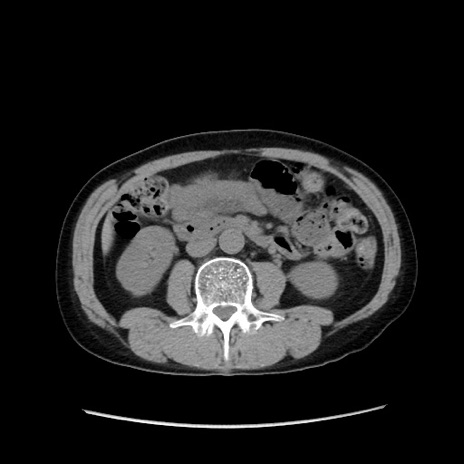

冠状断像

症例37(横断像)

【症例】40歳代 男性

【主訴】腹痛

【現病歴】4時間ほど前に電車に乗車中に臍部上より腹痛出現。徐々に増悪し起立困難となり、救急外来受診。生ものは数日食べていない。今朝お雑煮を食べた。

【身体所見】BT 36.8℃、BP 117/84mmHg、HR 91/min、SpO2 97%、苦悶様、腹部:臍上部広範囲圧痛あり、反跳痛±

【データ】WBC 8100、CRP 0.03